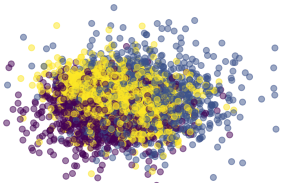

where the ReLU function forces the estimate of the KL divergence to be positive, thus avoiding to back-propagate wrong estimates of the density ratio due to the simultaneous training of . In (Abid & Zou, 2019), while Alg.1 of the original paper describes two distinct gradient updates, it is written that ”This discriminator is trained simultaneously with the encoder and decoder neural networks”. In practice, a single optimizer is used in their training code. In our work, we use an independent optimizer for , in order to ensure that the density ratio is well estimated. Furthermore, we freeze ’s parameters when minimizing the Mutual Information estimate. The pseudo-code is available in Alg. 1, and a visual explanation is shown in Fig.3.

Qualitatively, the model can be evaluated by looking at the full image reconstruction (common+salient factors) and by fixing the salient factors to for target images. Comparing full reconstructions with common-only reconstructions allows the user to interpret the patterns encoded in the salient factors (see Fig.1 and Fig.5).